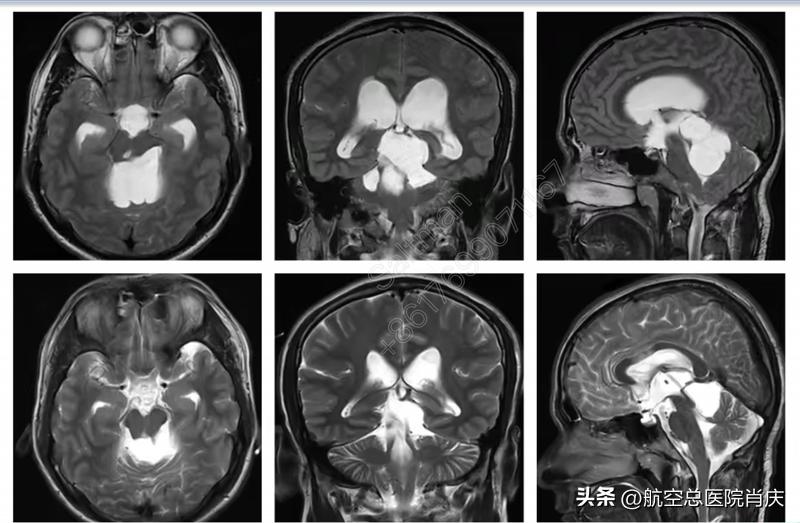

手术前后核磁对比

手术非常顺利成功,术后继续抗感染、营养神经等对症治疗。经过治疗,脑脊液逐渐恢复清亮,脑室外引流夹闭四日,患者病情稳定,头颅CT复查无明显扩张,囊肿较前缩小,后续进行了外引管去除术。